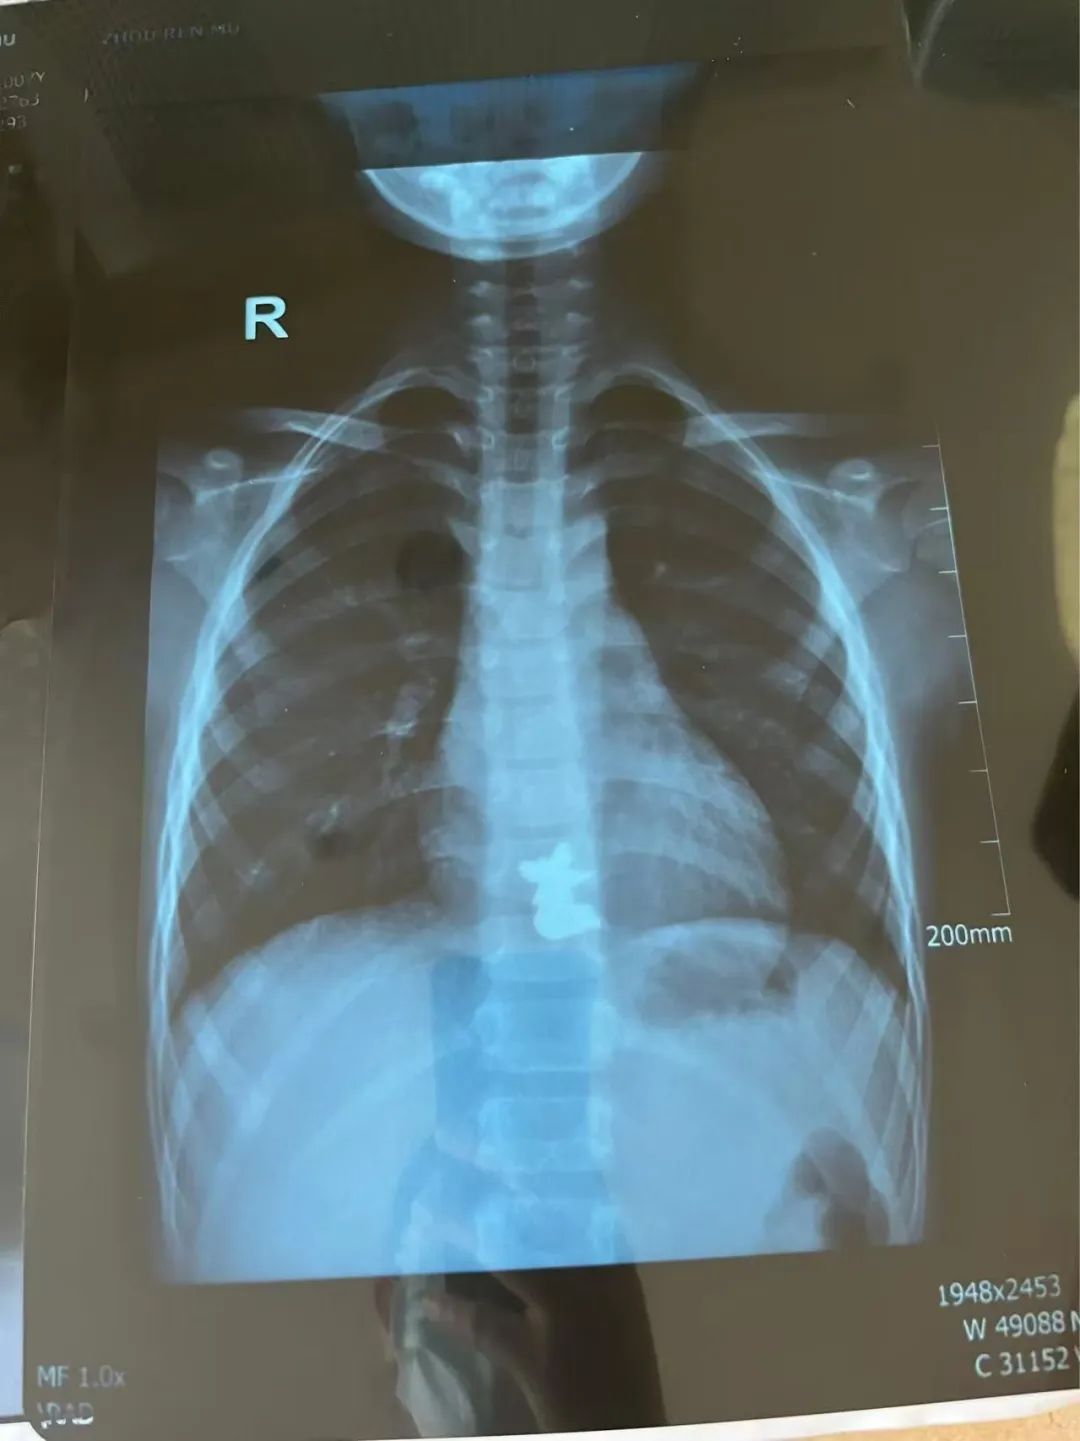

“腹腔镜进去后,发现第一枚磁铁是在升结肠的位置,第二枚磁铁在距离小肠的末端——回肠大概五六十厘米的地方,两枚磁铁紧紧地吸在一起,中间还夹住了一块小肠。”主刀医生普外新生儿外科袁亮主治医师说,取下磁铁后,发现四处肠穿孔,只有将坏死的肠管进行切除后缝合。